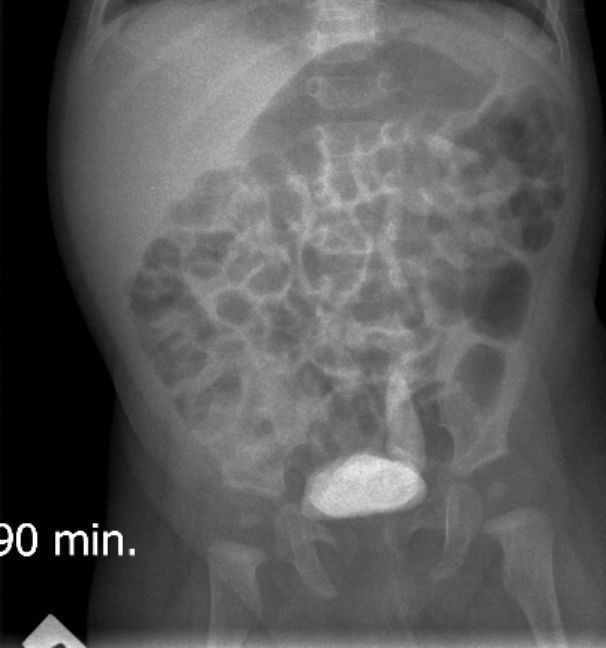

Экскреторные урограммы данного пациента :

На всех снимках определяется левосторонний уретерогидронефроз 3-й степени и левостороннее уретероцеле непостоянного размера. Справа - расширения собирательной системы почки не выявлено. На снимке на 15 минуте после введения контраста определяется уретероцеле справа небольших размеров, на последующих снимках достоверного его контрастирования нет.